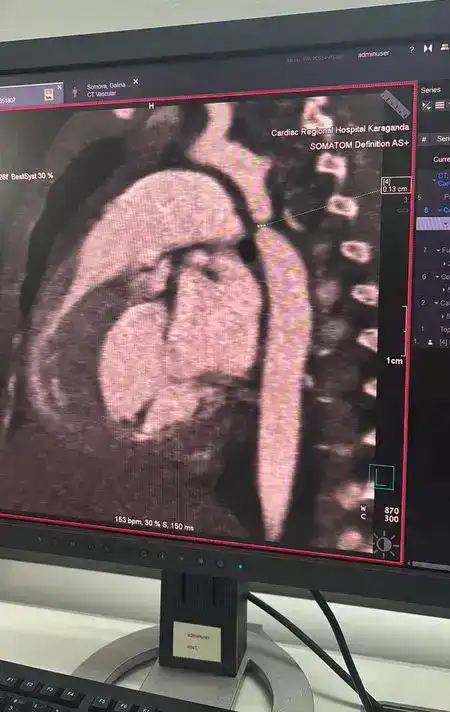

В Караганде команда врачей из многопрофильной больницы №2 (Кардиоцентр) успешно провела операцию на сердце трёхмесячной девочке с критической коарктацией аорты. Малышка была госпитализирована с диагнозом пневмония в многопрофильную больницу №1, где, в ходе обследования, врачи обнаружили опасный порок сердца, требующий срочного вмешательства.

Операция длилась почти пять часов, в ходе которой врачи выполнили резекцию коарктации аорты с наложением анастомоза «конец в конец», что позволило полностью восстановить кровоток. Также во время вмешательства был выявлен открытый артериальный проток, который был успешно легирован. По словам кардиохирурга Галымжана Утегенова, операция была технически сложной, но прошла в плановом режиме, и сейчас многое зависит от послеоперационного восстановления.